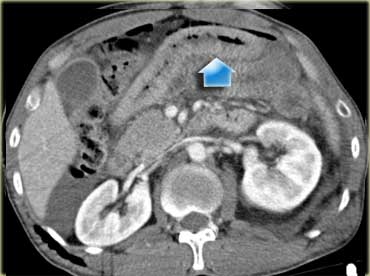

Các dấu hiệu bao gồm:

- Giảm tưới máu lách (mũi tên vàng).

- Nhiều vùng thoát thuốc cản quang (mũi tên xanh lá).

- Tràu máu ổ bụng và tràn khí ổ bụng.

- Nhiều đoạn ruột có thành dày lan tỏa (mũi tên xanh dương).